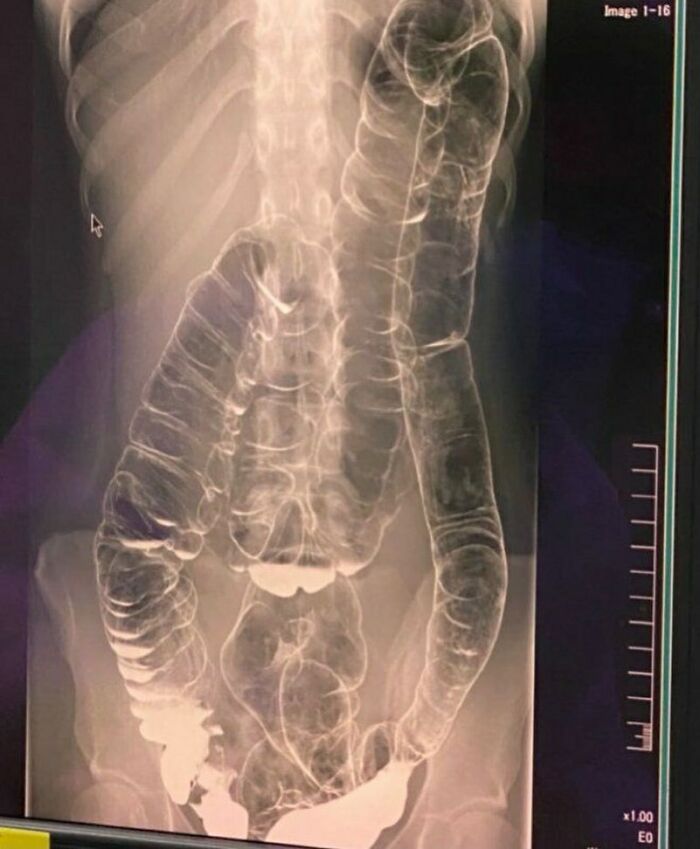

#28

This is what constipation after 19 days looks like. A woman suffering from chronic constipation, discovers her colon severely displaced.

Bowel obstruction, also known as intestinal obstruction, is a mechanical or functional obstruction of the intestines which prevents the normal movement of the products of digestion. Either the small bowel or large bowel may be affected. Signs and symptoms include abdominal pain, vomiting, bloating and not passing gas. Mechanical obstruction is the cause of about 5 to 15% of cases of severe abdominal pain of sudden onset requiring admission to hospital.

Causes of bowel obstruction include adhesions, hernias, volvulus, endometriosis, inflammatory bowel disease, appendicitis, tumors, diverticulitis, ischemic bowel, tuberculosis and intussusception. Small bowel obstructions are most often due to adhesions and hernias while large bowel obstructions are most often due to tumors and volvulus. The diagnosis may be made on plain X-rays; however, CT scan is more accurate. Ultrasound or MRI may help in the diagnosis of children or pregnant women.

The condition may be treated conservatively or with surgery. Typically intravenous fluids are given, a tube is placed through the nose into the stomach to decompress the intestines, and pain medications are given. Antibiotics are often given. In small bowel obstruction about 25% require surgery. Complications may include sepsis, bowel ischemia and bowel perforation.